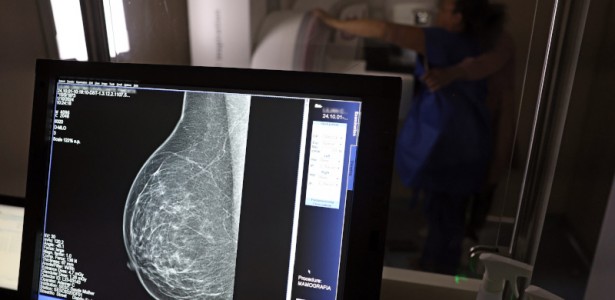

Desafios na Mamografia

Em relação ao câncer de mama, 170 mulheres entre 50 e 69 anos participaram do estudo. Embora 84% tenham realizado mamografia nos últimos cinco anos, elas também relataram dificuldades significativas. A dor durante o exame foi a principal barreira (59%), seguida pela longa espera para a mamografia (44%) e dificuldades de agendamento (40%).

“A dor no exame é um obstáculo significativo, indicando que experiências negativas podem ter um impacto duradouro sobre a disposição das mulheres em se submeter a exames futuros”, destaca Alice Barros Câmara, pesquisadora da Fosp.